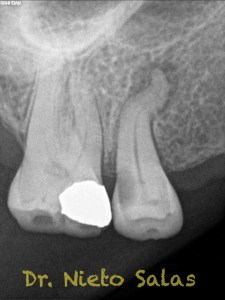

Conseguiríamos un sellado de esta manera en el caso A:

Y  de forma muy similar en el caso B; en este caso el paciente vino a la revisión a los 9 meses evidenciado el éxito en el tratamiento: